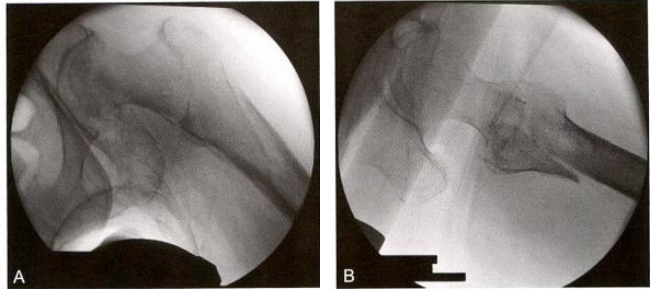

图9-9 用骨膜剥离子对移位的骨折块进行经皮撬拨复位。 A. 转子间骨折,牵引后颈 干角恢复;B. 近端仍有外旋,侧位透视股骨颈侧皮质向前移位成角,大转子向后移 位 ;C. 插入主钉后,侧位透视显示股骨颈侧皮质向前移位成角,导针在股骨颈内偏 前。用骨膜剥离子撬拨,复位股骨颈侧皮质,透视显示复位满意,成角消失,导针位 于股骨颈中央;D. 正 位 ;E. 侧位;F. 术中照片